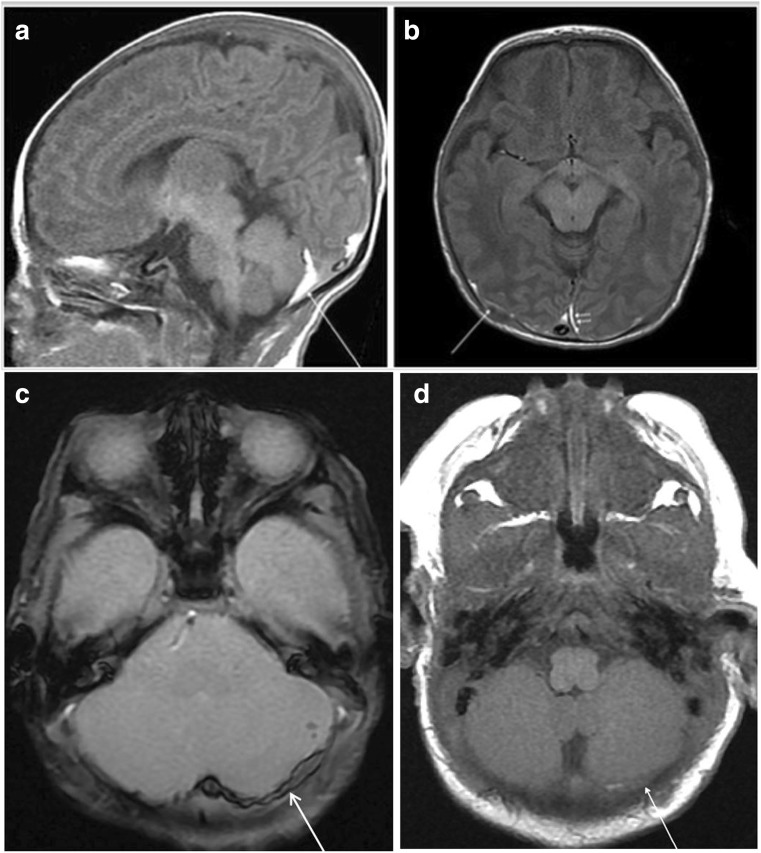

Fig. 1.

A 9-day-old male neonate exhibited supratentorial and infratentorial SDH, SAH, and intraparenchymal hemorrhage on imaging. He was born via spontaneous vaginal delivery at 38+6 weeks, weighing 2680 g. Within 24 h after birth, he developed apnea and seizures. Apgar scores at 1 and 5 min were 3 and 5, respectively. He was born to a primigravida with a history of prolonged labor. Ophthalmologic examination revealed the development of retinal hemorrhage in both eyes. His Bayley scale score at 8 months showed mild developmental delay. a Sagittal T1WI shows combined supratentorial and infratentorial SDH (arrow). b Axial T1WI imaging demonstrates a high-signal SDH over both parietooccipital lobes (arrow), and along the posterior interhemispheric fissure (arrowheads). c GE axial imaging shows puntate intraparenchymal hemorrhage of the left cerebellar hemisphere as well as SDH over the left cerebellar hemisphere (arrow). d SDH (arrow) had nearly resolved at the 1-month follow-up MR

MR imaging was performed 2–22 days postnatally (mean age at MR imaging 9.3 days). The involved compartments of ICH are summarized in Table 2. Ten term infants had infratentorial hemorrhage, whereas two had hemorrhage in the supratentorial region. A total of 30 neonates had a combination of both infratentorial and supratentorial hemorrhage (Fig. 1).